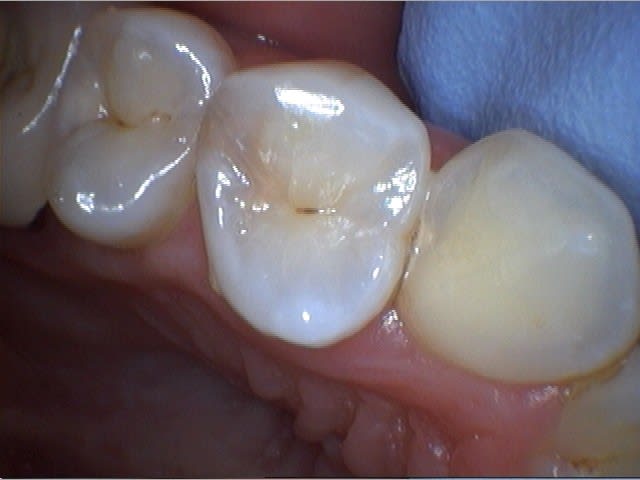

J'ai reçu la Camera intrabuccale 1/4 Sony CCD MD960u ce matin. Pas encore eu trop le temps de me pencher sur les réglage, mais voici ce que ça donne une fois installée et branchée...

Je trouve cela pas mal du tout pour une camera à 200€! :-)

Beaucoup mieux que la MD740, non?

Quelques photos prises ce matin au cours d'une longue séance de soins. Je posterais un test complet de la caméra bientôt pour ceux que ça intéresse...